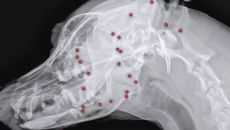

비비탄 이어 산탄총까지... 유기견에 박힌 총알 파편 70개 '충격'

해외 입양 절차 밟기 위한 검사 중 발견돼 1차 파편 제거 수술서 얼굴 쪽 26개 제거 "검사 결과에 따라 추가 수술 여부 결- 2025-06-25 17:00